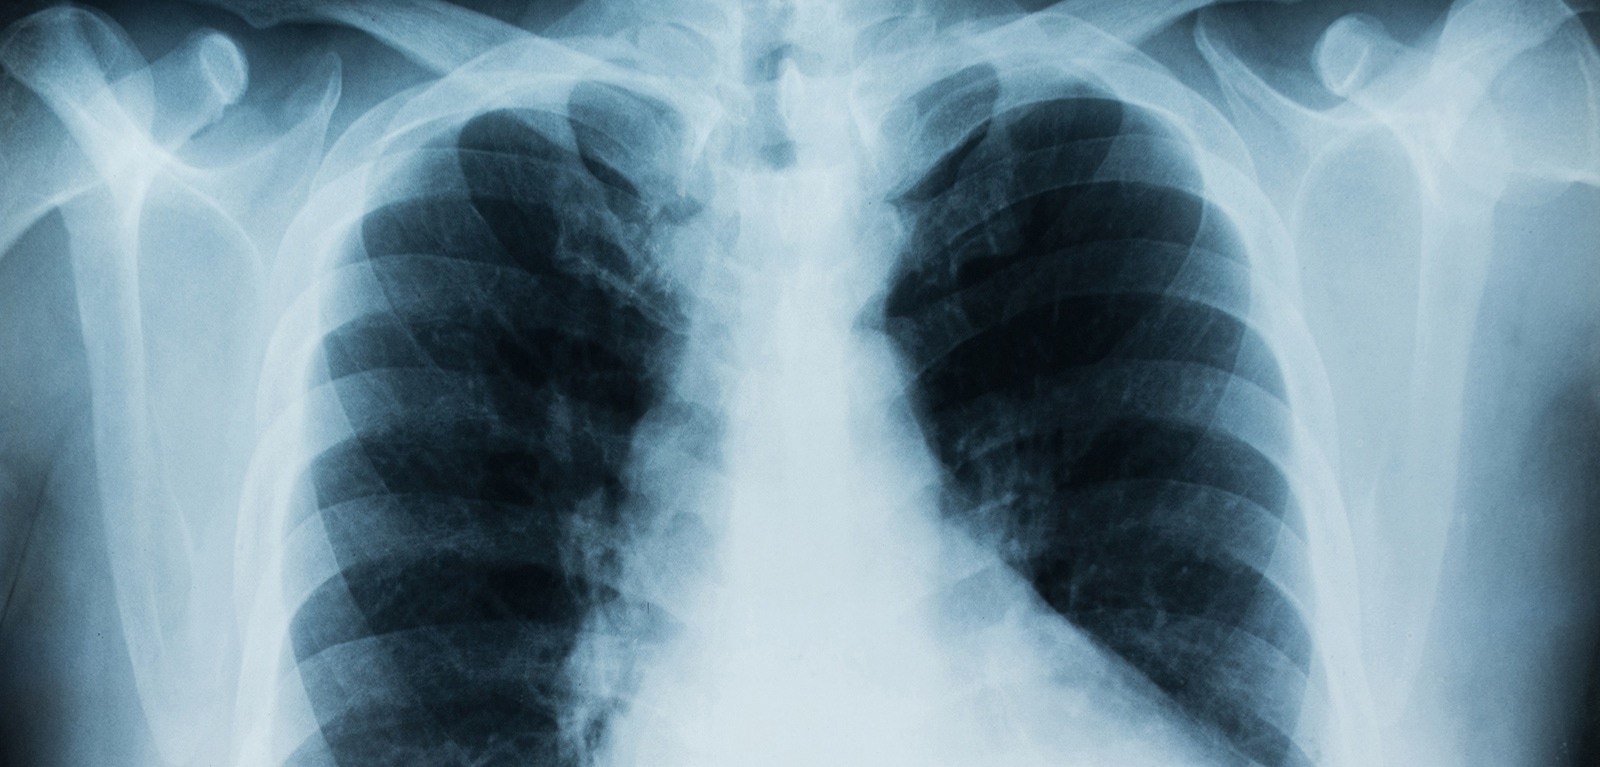

Image Credit: Queen’s University Belfast

To conduct their study the researchers looked at the bacterium Achromobacter which can cause chronic lung infection and tissue damage in the airways.